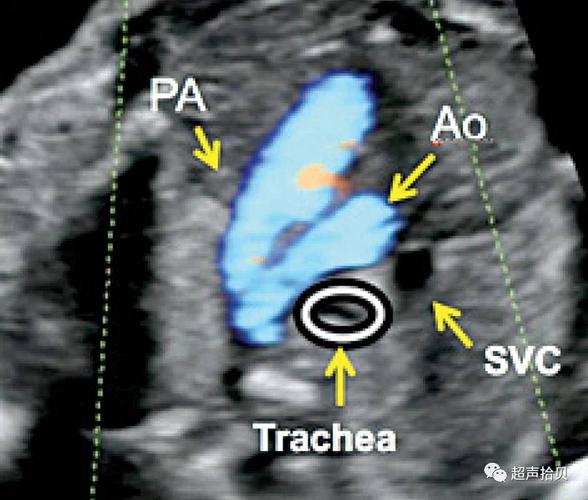

充分理解胎儿三血管气管切面(正常篇)

让我们一起再复习一下三血管气管切面在胎儿心脏疾病诊断的价值(1)

三血管及气管切面 短轴切面(心室及流出道) 主动脉弓 导管弓 上腔静脉

三血管气管切面示意图

三血管气管切面